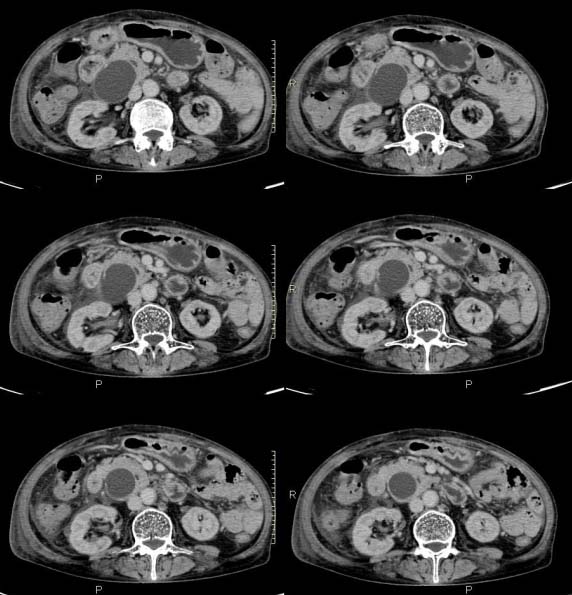

女,71岁,腹痛、腹胀、黄疸20余天,b超示肝内外胆管高度扩张内伴絮状物质(未提示梗阻部位或结石影),经抗炎解痉治疗后,肝功能有所好转,但胆道梗阻状态并未减轻。患者曾于1970年代做过胆囊切除术,1997年因胰腺炎而手术;且患者有糖尿病10余年。ct图片传了静脉期,未传动脉期了,最后一序列为3.2mm薄扫,请各位同仁仔细看看,确定一下胆管梗阻的部位,是炎性梗阻还是肿瘤性梗阻,是否与胰腺炎有关系,扩张胆总管中段前缘是否是胰管。请高手们最好用图示来指出梗阻部位。

扩张的胆管直达胰头,但胰头增大又不明显,且无异常密度影。考虑壶腹部占位。

请大家看看扩张的胆总管内见一弧线形间隔,怎样解释?

肝内外胆管显著扩张,考虑先天性胆管囊肿(ⅳ型)。

肝内胆管远侧、近侧不比例扩张,以近侧为明显。胆总管扩张。考虑先天性胆管囊肿(ⅳ型)。